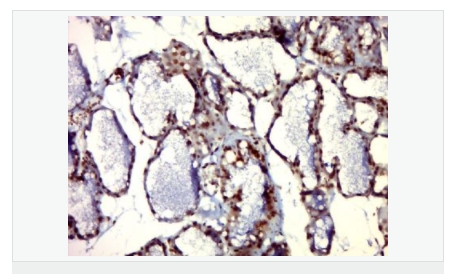

英文名稱Phospho-PIM1 (Tyr309)

中文名稱磷酸化前病毒整合位點蛋白1抗體

PIM1蛋白是絲氨酸/蘇氨酸蛋白激酶2家族成員,他參與細(xì)胞信號轉(zhuǎn)導(dǎo)、細(xì)胞凋亡、轉(zhuǎn)錄調(diào)節(jié),在很多腫瘤中表達(dá),尤其是前列腺癌,表達(dá)水平較高。